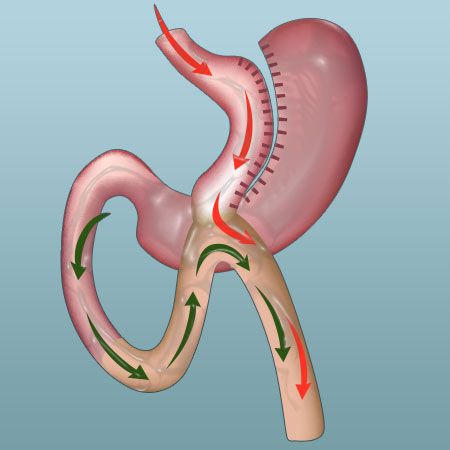

- Mini Gastric Bypass

| Mini-Gastric Bypass | $4,999 USD | 4 days 3 nights |